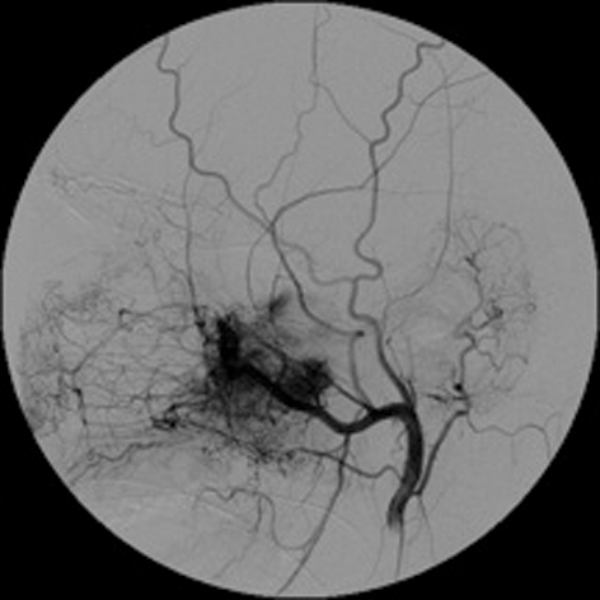

Role of interventional neuroradiology in otorhinolarygological pathology – a brief review

Introduction Since its advent in 1964 when Dotter percutaneously dilated a stenosed femoral artery [1], interventional radiology has undergone tremendous advancement in both imaging and devices that have enabled the operator (interventional radiologist) to access very distal small vasculature and...